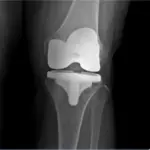

📌 2만례 이상의 어깨, 무릎 수술 경험

📌 척추관절, 비수술부터 수술, 재활까지